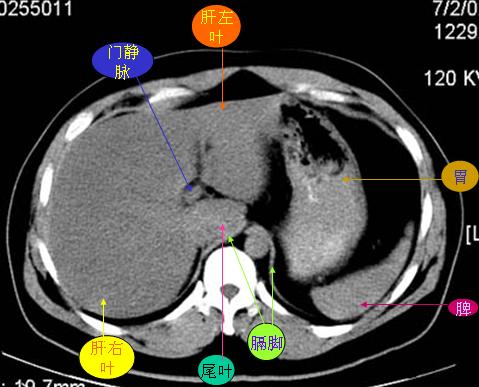

腹部ct解剖与基本病变